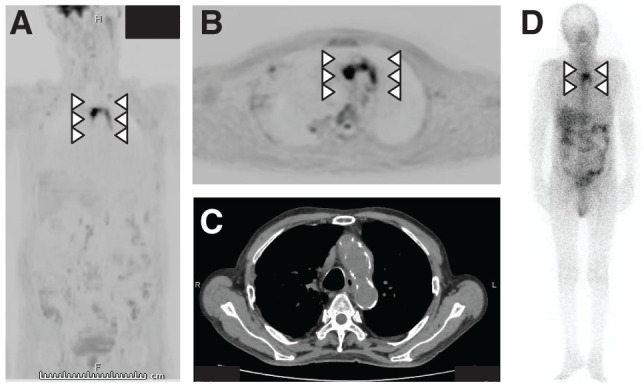

Diffusion-weighted whole-body imaging with background body signal suppression has been used to diagnose fever of unknown origin. An 86-year-old man who underwent bile duct jejunostomy for bile duct cancer presented with fever (body temperature, 40°C). Escherichia coli was detected in blood cultures. Diffusion-weighted whole-body imaging with background body signal suppression revealed accumulation in the aortic arch. Therefore, infectious aortitis secondary to retrograde cholangitis was diagnosed. The patient was treated with antibiotics, and the aortic arch accumulation disappeared. Diffusion-weighted whole-body imaging with background body signal suppression is a useful modality for diagnosing vasculitis and assessing treatment effectiveness.